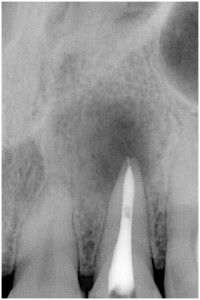

歯髄壊死 左上の前歯 川口の歯科 歯医者 さかえ歯科クリニック

2014年12月16日

術 前 術 後